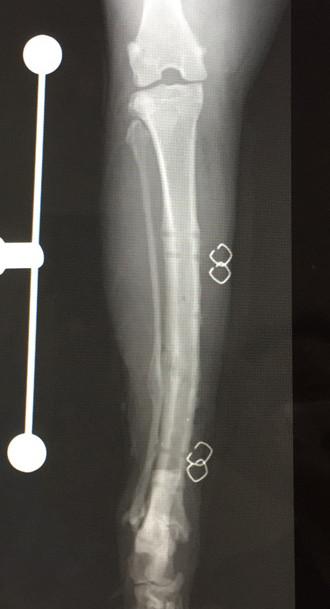

7月17日 手術から 12ヶ月 後

2回目のプレート抜去

メインプレートとボルト4本抜去。

8月21日 手術から 13ヶ月 後

札幌の病院で経過観察、骨形成OKで問題なし。